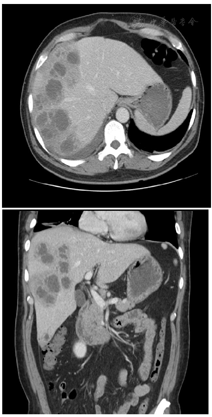

病例2,入院体格检查:体温36℃,脉搏92次/min,呼吸18次/min,血压96/79 mmHg,体质量75 kg。神志清楚,精神好。体格检查:普通视力检查:右手动/10 cm,左0.4眼压检查(非接触式眼压计);右Tn左11 mmHg裂隙灯检查:右眼:眼睑无水肿、充血、破溃、裂伤,结膜混合充血,角膜内皮可见大量菌栓附着,巩膜无黄染、结节,房闪(+++),虹膜:纹理清,无前粘,后粘,色泽正常,圆,居中,光敏,瞳孔药物性散大,晶状体密度增高,前囊可见渗出膜,玻璃体:积脓。间接眼底镜检查:视不清。裂隙灯检查:左眼:眼睑无水肿、充血、破溃、裂伤,结膜无明显充血,角膜透明,巩膜无黄染、结节,前房深度可,房闪(-),虹膜:纹理清,无前粘,后粘,色泽正常,瞳孔大小3 mm×3 mm,圆,居中,光敏,晶状体密度增高,玻璃体:混浊;间接眼底镜检查:小瞳下网膜未见明确出血及渗出。诊断:右眼EE。余心肺腹体格检查无特殊。实验室检查:乙肝、丙肝、HIV阴性;尿常规、甲功五项、糖化血红蛋白阴性、脑脊液正常、阴性。肿瘤标志物:血清铁蛋白1109 ng/ml;结缔组织疾病阴性;血常规:白细胞18.13×109/L↑,中性粒细胞占比0.848↑,血红蛋白111.00 g/L↓,血小板计数418.00×109/L↑;2022年8月1日门诊红细胞沉降率测定:58.00 mm/h↑;急诊炎症因子组合:C反应蛋白(干化) >90.00 mg/L↑,白细胞介素6 107.5 pg/ml↑,降钙素原全定量1.14 ng/ml↑。血培养、肝脓肿脓液培养:肺炎克雷伯菌(全敏感)。余心肺腹体格检查无特殊。头颅及腹部MRI:(1)脑MRI平扫及增强扫描未见明显异常;(2)右侧眼环增厚,右侧视网膜脱离,右眼玻璃体内异常信号,右侧泪腺及右侧眼眶周围软组织水肿,考虑炎性改变,请结合相关专科检查;(3)肝内多发异常信号,结合病史,考虑多发肝脓肿,肝门区及腹膜多发淋巴结,部分肿大;(4)胆囊炎;(5)肝周少量积液;(6)扫及双侧胸腔少量积液;扫及右肺内异常信号,建议结合胸部CT检查。腹部CTA提示:(1)肝内散在低密度灶,考虑脓肿可能,请结合临床;(2)胆囊炎;副脾;(3)腹膜后散在淋巴结;(4)右侧胸腔积液并部分肺不张,左侧胸膜不均匀性增厚;(5)腹部CTA示左肾双支肾动脉,第三肝门显影。超声造影:肝实质内多发混合性占位灶并其内多发分隔,结合超声造影考虑:肝脓肿并部分液化(图4、图5)。